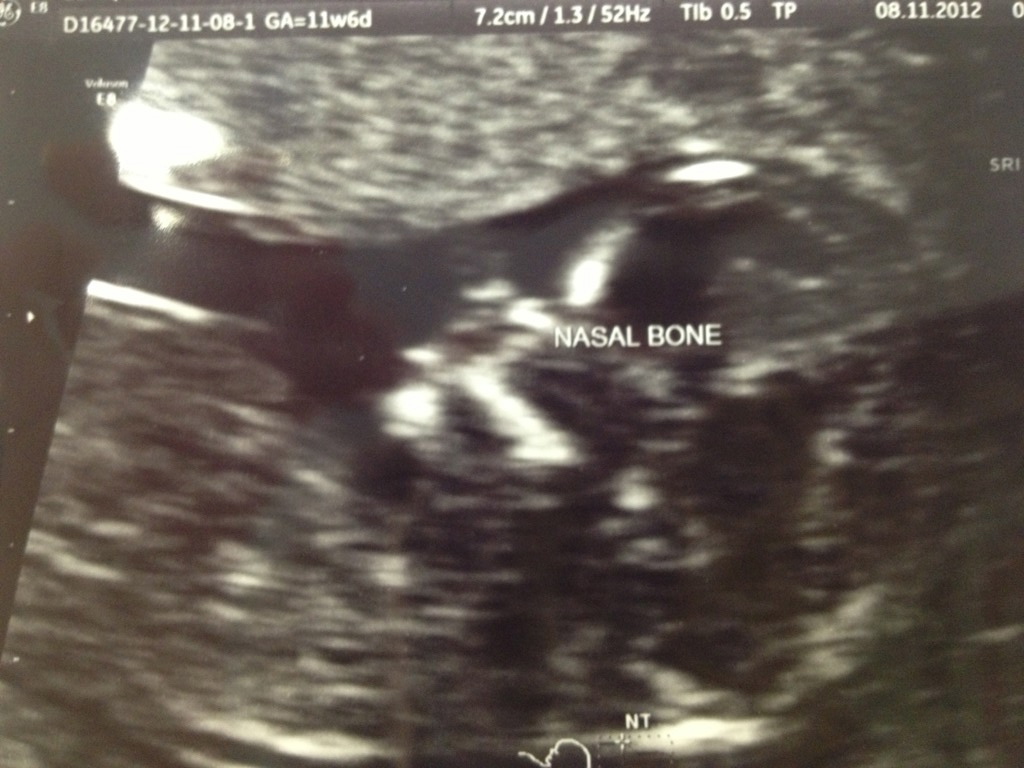

Hi girls, here is a pic that I think might be nub? The tech refused to give me any potty shots or nub shots but I think this one might show it?

Have a couple more and will post later but I think this is the clearest. Would love to know your guesses please :)